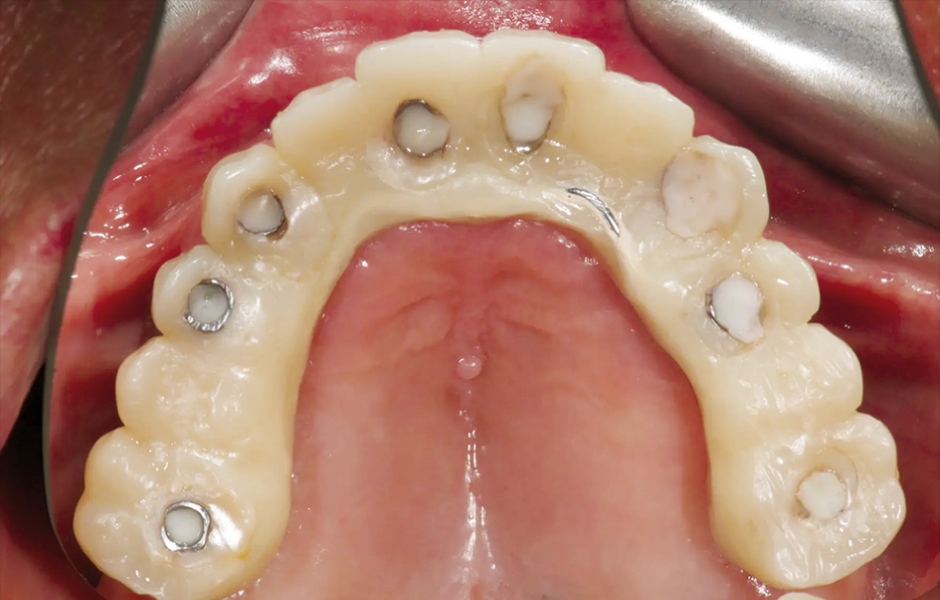

V den operace byla aplikována lokální anestezie a první chirurgická šablona byla stabilizována na zbývajících zubech k přípravě pěti fixačních pinů. Poškozené zuby byly extrahovány a druhá chirurgická šablona byla upevněna v připravených místech. Osm implantátů (Osstem TSIII SOI, Osstem Implant) bylo umístěno – pět do čerstvých extrakčních alveolů a tři do dříve zahojených oblastí. Všechny implantace proběhly plně navigovaně pomocí chirurgické šablony bez kovových pouzder a s dedikovanou chirurgickou sadou (OneGuide KIT, Osstem Implant; obr. 8). [11] Jeden implantát vyžadoval krestální sinus lift, který byl proveden plně navigovaným přístupem (OneCAS KIT, Osstem Implant; obr. 9). Xenogenní kostní materiál (A-Oss, Osstem Implant) byl použit k vyplnění extrakčních alveolů a dutiny sinu. [12] Na všechny implantáty byly okamžitě nasazeny multi-unit abutmenty a dočasné abutmenty (Osstem Implant) podle konceptu „one abutment, one time“. [13] Předem připravená dočasná protetika na bázi PMMA s kovovou výztuhou byla vložena a ihned fixována v ústech. V ordinaci byly provedeny úpravy pro dosažení správné okluze (obr. 10–12). Pacient obdržel pooperační instrukce a medikaci.

Obr. 10: Provizorní protetická práce s kovovou výztuhou.

Obr. 11: Provizorní protetická práce s kovovou výztuhou in situ, čelní pohled.

Obr. 12: Provizorní protetická práce s kovovou výztuhou in situ, okluzální pohled.